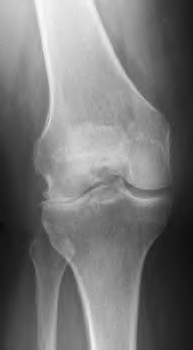

A 55-year-old male presents with isolated medial compartment osteoarthritis of the right knee. He is being evaluated for a medial unicompartmental knee arthroplasty (UKA). Which of the following physical examination or radiographic findings is an absolute contraindication to a medial UKA?

When planning a medial opening wedge high tibial osteotomy (HTO) for isolated medial compartment osteoarthritis in a varus knee, the surgeon intends to shift the mechanical axis to the Fujisawa point. Where is the Fujisawa point located on the tibial plateau?

Which of the following is traditionally considered an absolute contraindication to a medial mobile-bearing unicompartmental knee arthroplasty (UKA)?

When evaluating a patient for a Unicompartmental Knee Arthroplasty (UKA), which of the following is considered a classic absolute contraindication?

A 52-year-old male with isolated medial compartment osteoarthritis is evaluated for a unicompartmental knee arthroplasty (UKA).